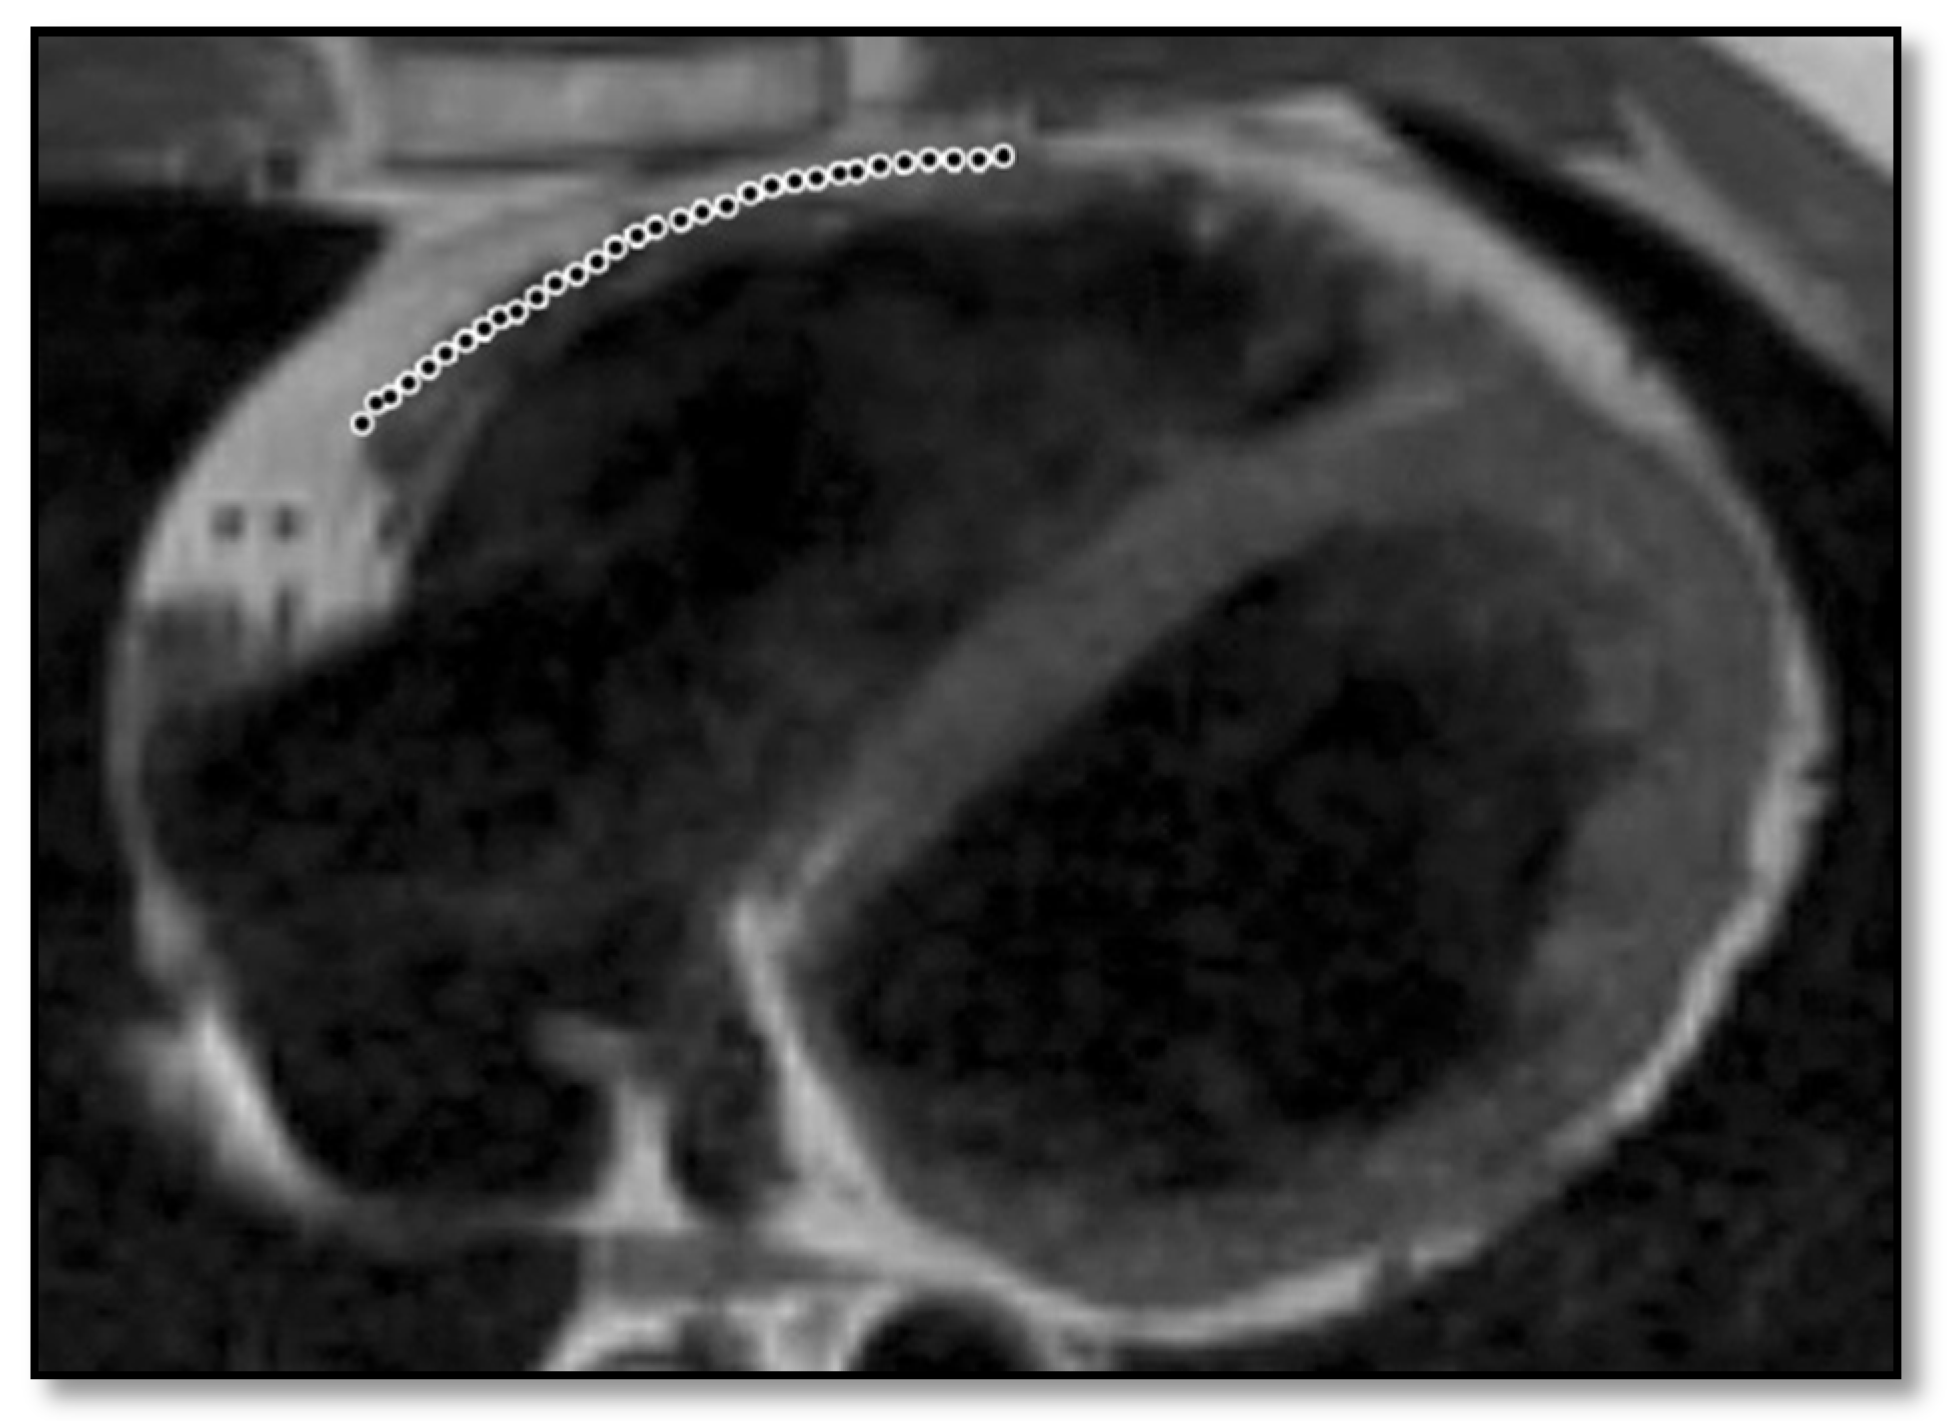

| 3 | Short-axis images | Another limitation of cardiac MRI comes from the scarce analysis of short-axis images. The incidences are used for the correct assessment of the right ventricular size. If short-axis images are not used, there is a 20% chance that the radiologist will incorrectly measure right ventricular size and inadvertently assuming RV dilation [86]. |

- RV contraction disorders and functional abnormalitiesUnlike the initial diagnostic criteria, the 2010 Revised Task Force Criteria [12] are quantitative rather than qualitative. Three types of changes were included: (1) segmental RV contraction abnormalities, (2) dilation of the RV, and (3) reduction of the RV ejection fraction. It is notable that intramyocardial fat or delayed enhancement are not included in the criteria for differential diagnosis strictly because these changes can be found in healthy people or in other diseases affecting the right ventricle. The association between akinesia/dyskinesia or RV regional contraction asynchrony with RV volume dilation or RV ejection fraction <40% is considered a major criterion for the diagnosis. As mentioned beforehand, the Revised Criteria are quantitative. Therefore, RV dilation is defined as the ratio of RV volume/body surface area > 110 mL/sqm in men or >100 mL/sqm in women. The minor criterion is defined as the presence of akinesia/dyskinesia with decreased ejection fraction of 40 to 45%, contraction abnormalities, or increased RV volume between 100 and 110 mL/sqm in men or 90 and 100 mL/sqm in women. It is worth noting that microaneurysms as well as segmental RV dilatations were removed from the Diagnostic Criteria because they are rather subjective and challenging to evaluate.